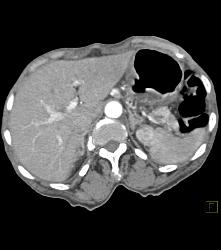

Gastric Adenocarcinoma With Celiac Nodes